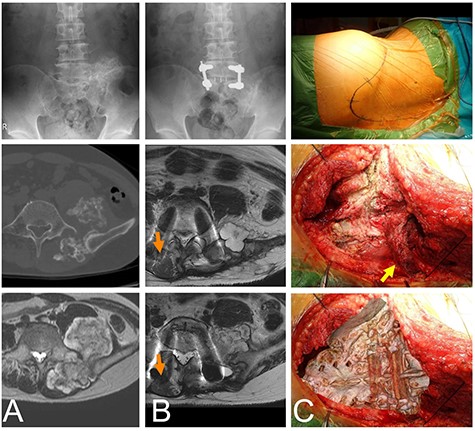

A 44-year-old male initially presented with pain in his lower extremity. He visited a nearby hospital that referred him to our institute where a working diagnosis of a bone tumor was made. The plain radiograph shows an osseous lesion on the left posterior pelvis. Computed tomography (CT) depicted an osseous lesion arising from the left sacral ala. The osseous lesion was covered by a layer with intermediate signal intensity on the T1 weighted image and high signal intensity on the T2 weighted image from magnetic resonance imaging. The diagnosis from the image was an osteochondroma, which was covered by a cartilaginous cap. The maximum size of the tumor was ~6 cm and the thickness of the cartilaginous cap was <2 cm (Fig. 1A). The histology of the needle biopsy of the cartilaginous cap showed a proliferation of chondroid tissue without atypia, suggesting an osteochondroma.

Chondrosarcoma in the sacrum of a 44-year-old male. A plain radiograph (A, top) and CT (A, middle) shows an osseous lesion in the sacrum. The osseous lesion is covered by a cartilaginous lesion with a high signal T2 weighted image (A, bottom). L5 and S1 were fused with screws in the initial operation (B, top). Eleven months after the initial operation cartilaginous nodules appear as a recurrent lesion at L5 (B, middle) and S1 (B, bottom). The once elevated distal multifidus muscle on the non-tumor side was morphologically almost normal (orange arrows), but the distal multifidus muscle on the tumor side was still thin. The patient was in the right-side bottom decubitus position. The skin marker shows the convex skin incision at the distal sacrum posteriorly (C, top). The sacrum is viewed by retraction of the multifidus muscle (yellow arrow) (C, middle). The image of the sacrum is overlapped on the C-middle picture to show the anatomical location (C, bottom).

On diagnosis of the osteochondroma, a resection was performed. With the patient in the lateral position, a skin incision was made along the iliac crest to the contralateral paravertebral muscle, with a distal convex shape at the sacrum. The distal multifidus muscle was detached from the lamina of the sacral and lumber vertebrae. The posterior ilium and vertebrae were exposed, and the tumor was resected. Following resection, a vertebral fusion between L5 and S1 was performed using pedicle screws (Fig. 1B). No complications associated with the operation appeared. The pathological diagnosis of the resected material was osteochondroma. The patient was able to walk without a crutch though dull back pain existed 6 months after the surgery with the degree of the pain getting worse. Image analysis 11 months after the initial operation revealed new cartilaginous nodules. The distal multifidus muscle on the tumor side was still thin, but the distal multifidus muscle on the non-tumor side was morphologically almost normal (Fig. 1B).

A needle biopsy of the new tissue revealed no atypical cartilaginous tissue. However, taking into consideration the clinical course, chondrosarcoma was diagnosed. Surgery was performed with almost the same incision, but the incision was extended to the distal sacrum (Fig. 1C). The multifidus muscle was removed from the distal sacrum in the same way as in the primary operation (Fig. 1C). The tumor compressed the L5 nerve root and was resected in several blocks. The pathological diagnosis of the resected material was a chondrosarcoma arising from the osteochondroma (Fig. 2). The pain was relieved postoperatively.